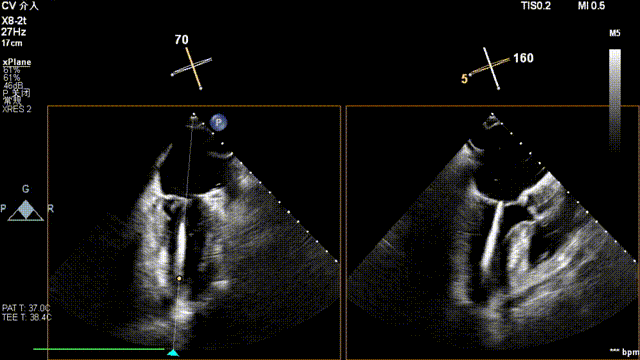

术中超声(关键步骤)

全麻后,二尖瓣夹合器系统在心前区的肋间切开3-4CM小切口,暴露心脏的心尖位置,送系统送入左心房,顺利到达病变二尖瓣区域。在经食道超声辅助下,术者通过反复评估二尖瓣反流位置、抓捕位置、反流程度,首先在2偏3区位置处于二尖瓣闭合线垂直进行巧妙夹合。在2区靠近3区位置处植入了1枚ValveClamp®MVC-IIf夹,最终评估评估反流降至轻度,平均跨瓣压差降至2mmHg,手术取得圆满成功。

最终在A3P2位置夹合,前叶夹合量10mm,后叶夹合量8mm,剩余瓣口面积3.45cm²,平均跨瓣压差2mmHg,反流基本消除。